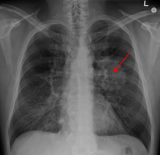

Clinical Oncologist at the Korle Bu Teaching Hospital, Dr Nana Ama Wadee, has raised concern over Ghana’s rising lung cancer deaths, warning that many patients are dying because the disease is often detected too late.